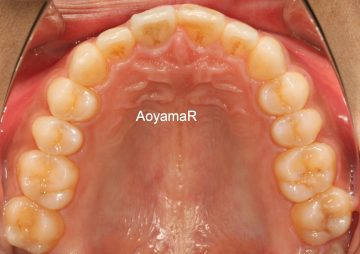

上顎前突(出っ歯、小さい下顎)の矯正症例

(17歳 男性 )

マウスピース型カスタムメイド矯正装置(インビザライン)単独による治療

治療前

治療後